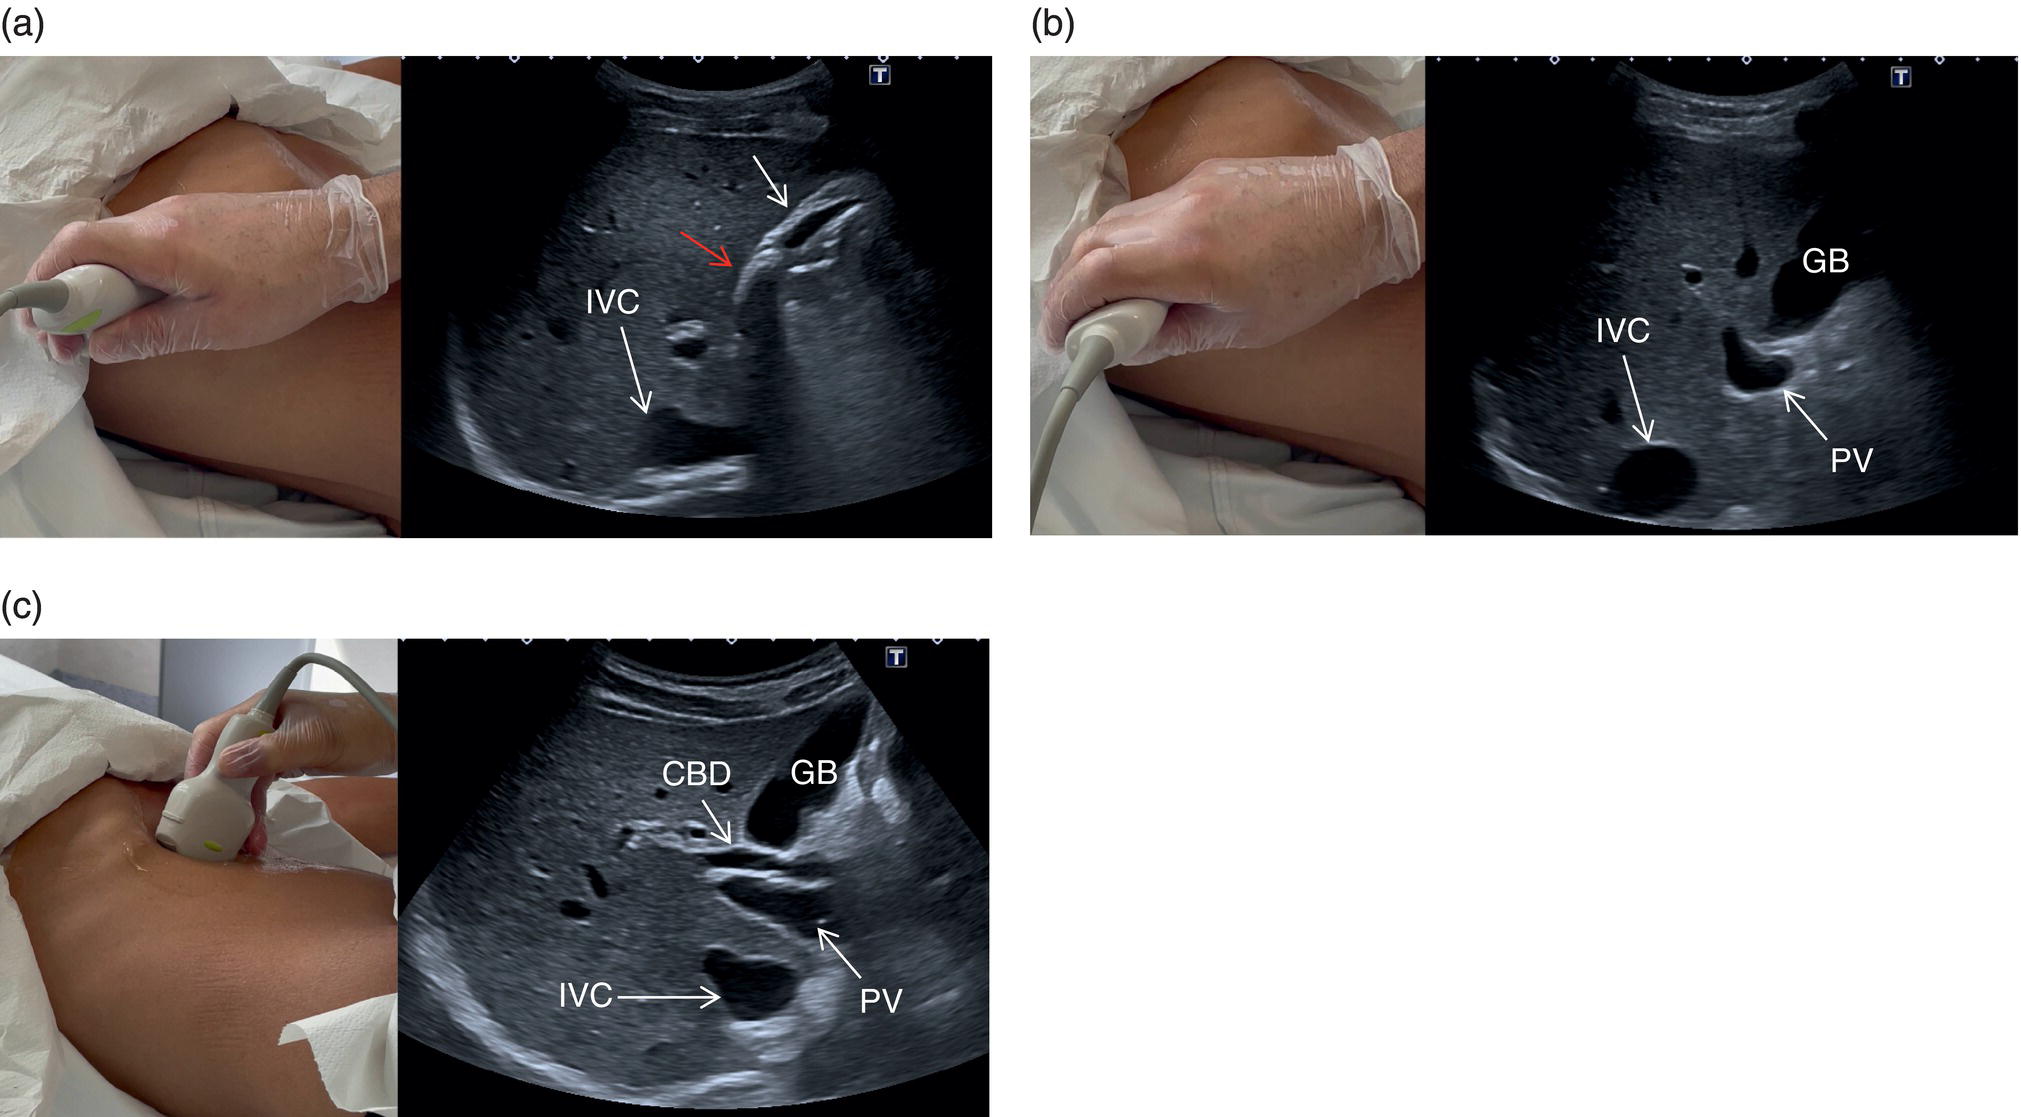

Gallbladder and Common Bile Duct

The GB is assessed in the subcostal position, in two orthogonal planes, and also intercostally. As a first approach, place the transducer on the anterior abdominal wall along the mid‐clavicular line, adjusting its position until the GB is located. Ask the patient to take a deep breath to lower the diaphragm and push the liver downwards below the costal margin; this will facilitate GB visualisation. It is essential to image the GB in its entire long axis and to angle the transducer so that it is also imaged transversally. The longitudinal intercostal approach will complete the GB visualisation, also offering an alternative to a sometimes challenging subcostal view in case of bowel gas interposition (Figure 3.27) (Video 3.9). In other circumstances, especially in the presence of narrow intercostal spaces, an intercostal approach might not be ideal. The CBD is best visualised with the patient supine or slightly turned with the left side down. Start with the probe obliquely positioned in the epigastrium, in line with the anatomical plane of the CBD. Sweep subcostally and outwards until you see the image of the portal triad (Figure 3.28). This may require some fine adjustments of the probe position (Video 3.10). The CBD is usually measured longitudinally where the HA intersects the CBD and PV; nevertheless, if the CBD shows some size variations it should be measured at the level of its maximal calibre (Figure 3.29). As for the GB, there may be occasions, owing to bowel gas, in which the CBD is better visualised in the anterior intercostal plane (Figure 3.30). ![]()

In normal physiological conditions, the CBD is the only biliary duct that can be clearly seen as a thin tubular structure with echogenic walls that in the majority of cases runs anteriorly and parallel to the PV at the level of the hepatic hilum (Figure 3.8). However, the anatomical relationship of the biliary ducts and the portal vessels may vary along their course, and usually the peripheral biliary ducts (which are only clearly visible when dilated or significantly thickened) run posteriorly to the PV (Figures 3.9 and 3.10).

The CBD measures between a minimum of 2–3 mm and an upper limit of 6–7 mm. Larger calibres are observed, especially post cholecystectomy and with age, where it is generally accepted that the calibre may increase by 1 mm each decade after 70 years [3].